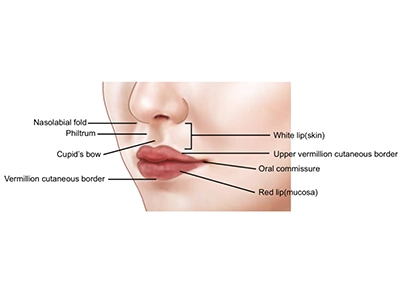

تقارن پرههای بینی و بهبود زاویه بینی و لب بالا